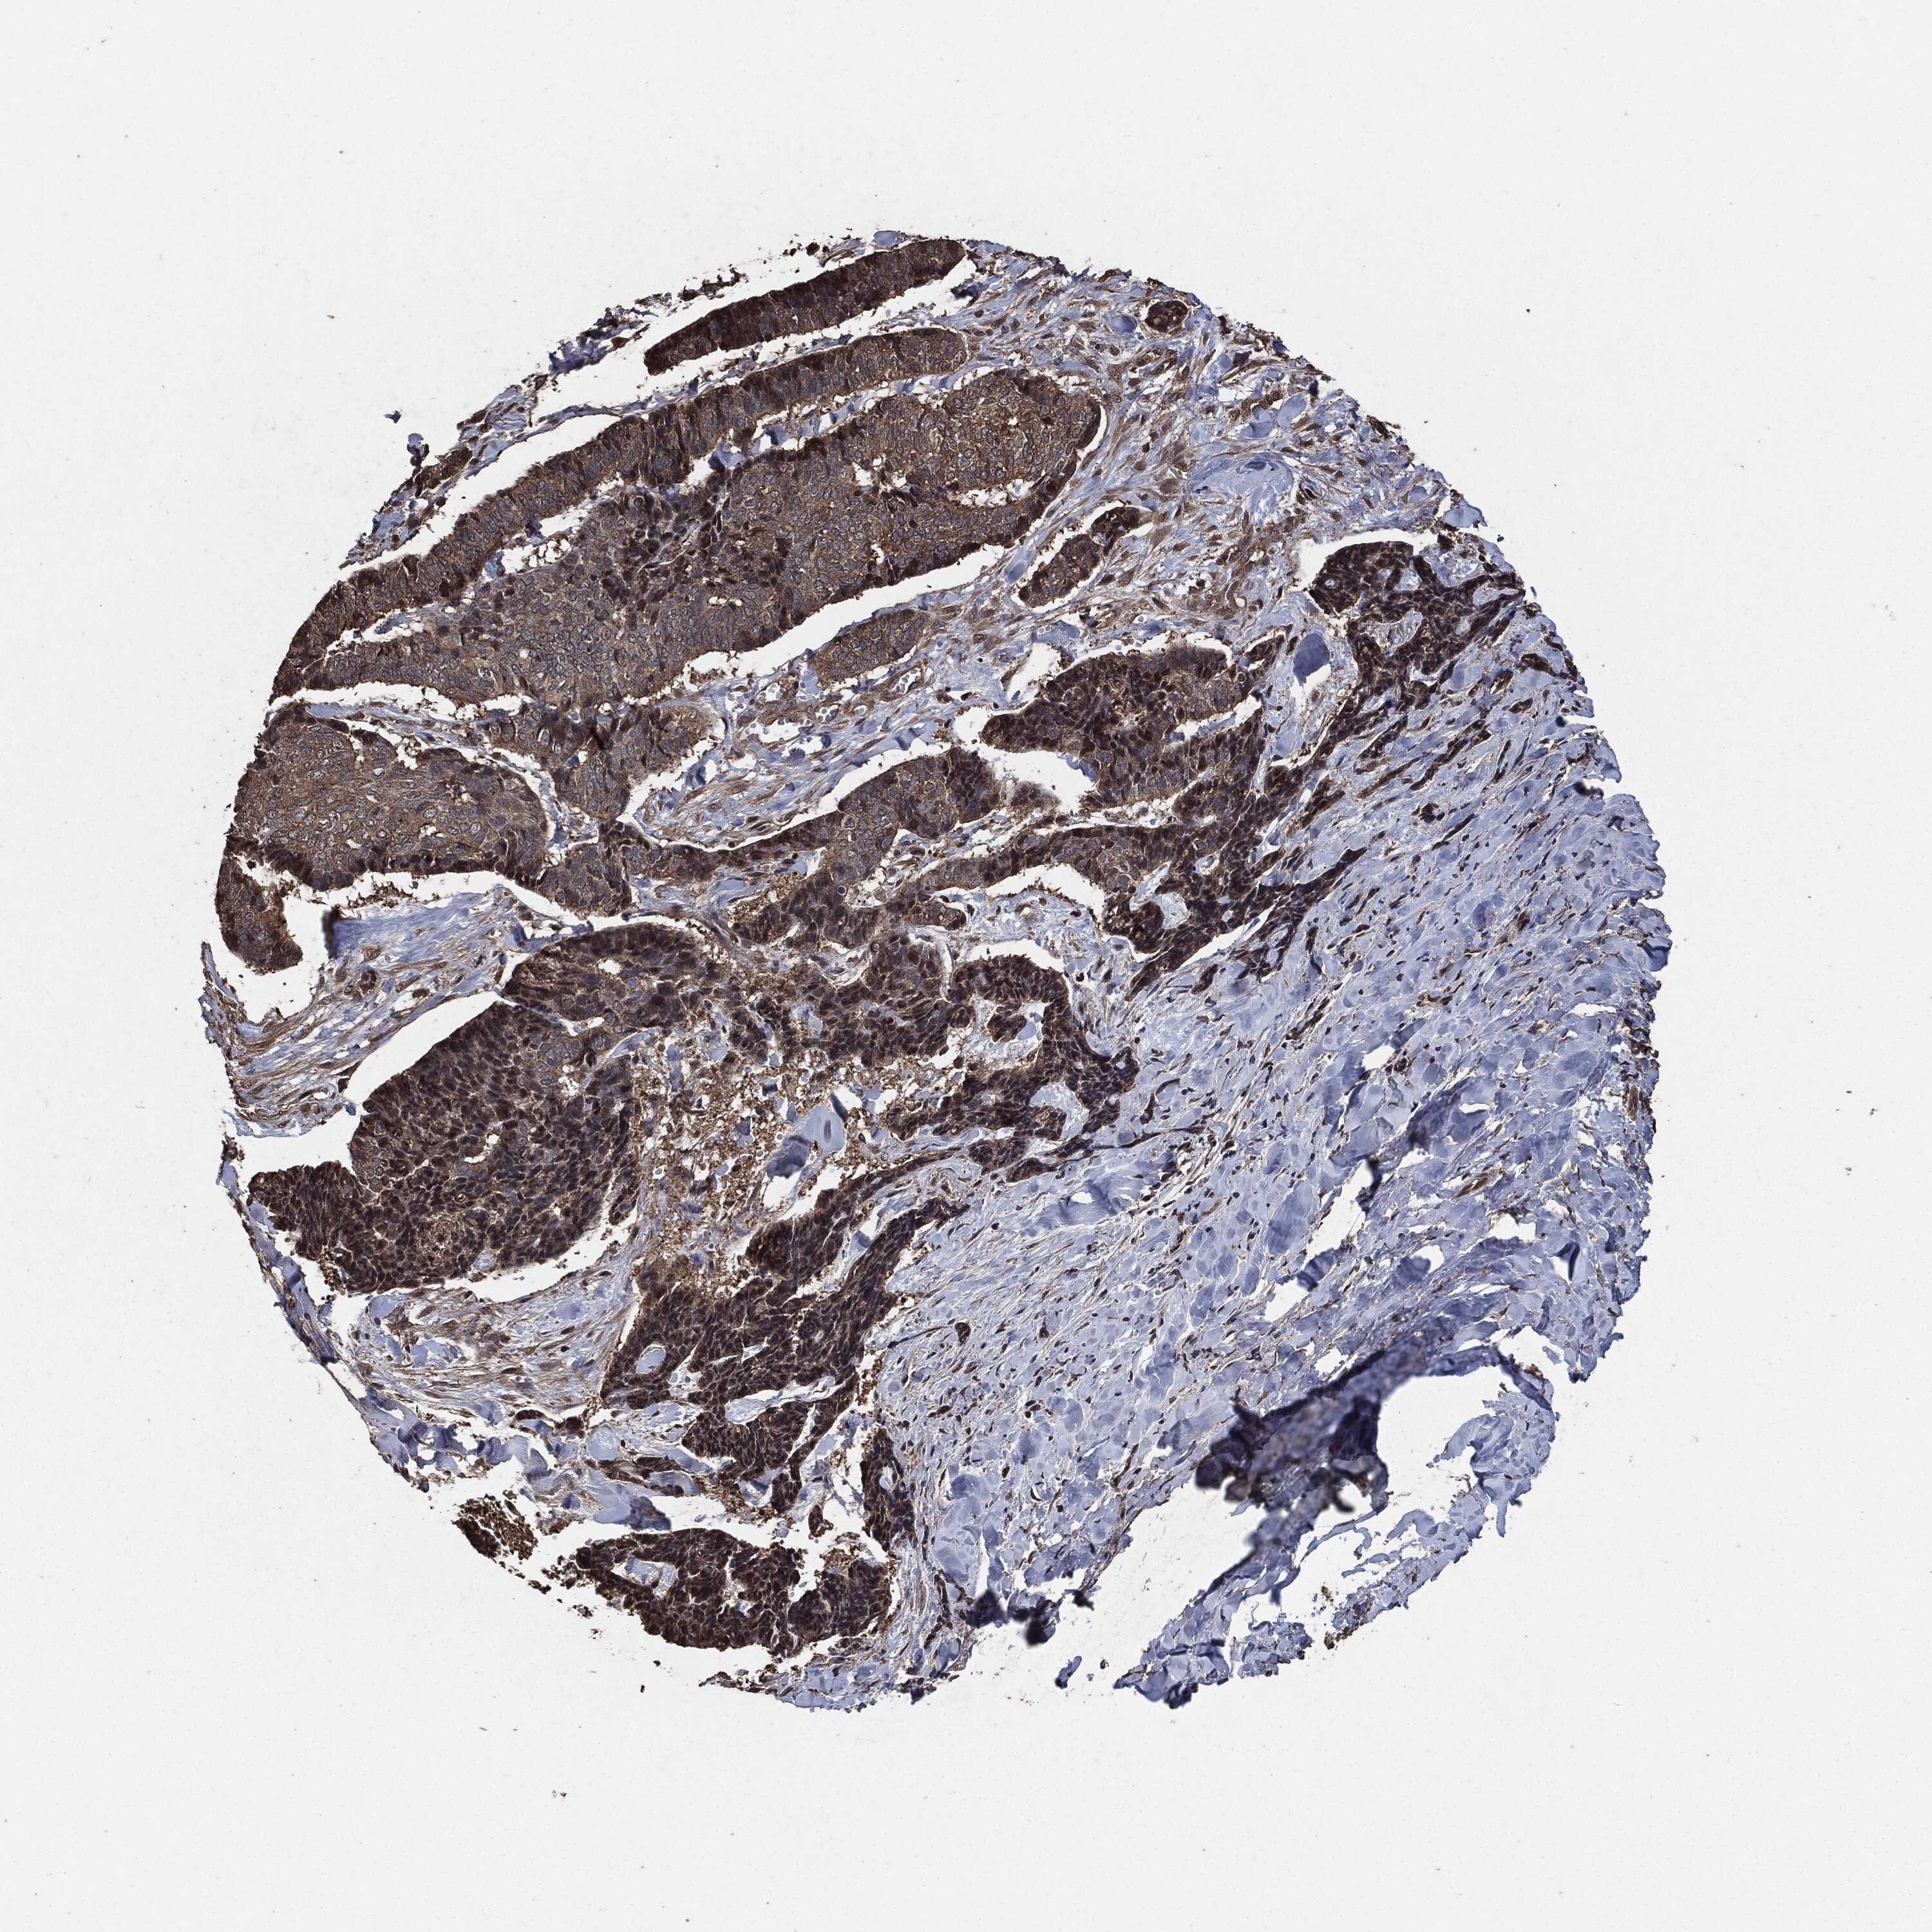

SKIN CANCER - Protein expressioni

A mouse-over function shows sample information and annotation data. Click on an image to view it in a full screen mode. Samples can be filtered based on level of antibody staining by selecting one or several of the following categories: high, medium, low and not detected. The assay and annotation is described here.

Each image is clickable and will lead to virtual microscopy that enables deeper exploration of all samples and also displays staining intensity scores, fraction scores and subcellular localization as well as patient and tissue information for each sample.

Antibody HPA075510

Staining

High

Medium

Low

Not detected

Intensity

Strong

Moderate

Weak

Negative

Location

Nuclear

Cytoplasmic/membranous

Cytoplasmic/membranous,nuclear

None

Basal cell carcinoma

BCC, high aggressive

Squamous cell carcinoma, NOS